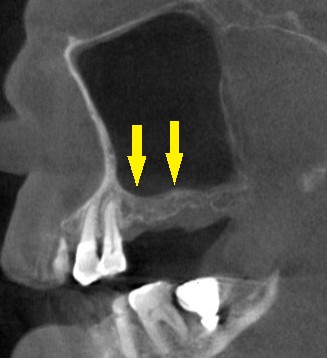

レントゲン、CTを撮影すると、骨幅は十分ですが、高さが3~4mmと、通常のインプラント埋入を行なうには、かなり不足でした。

何らかの骨造成が必要なのですが、年齢も考えて、あまり大変なことはしたくないとのご希望でしたので、人工骨を補填しての骨造成は行わず、ワイドショートインプラントで対応させていただくこととしました。

本日、左第一大臼歯に直径6.0mm長さ7mm、第二大臼歯部位に直径5.0mm長さ7mm、のインプラント埋入術を施行しました。

下の写真が手術前後のCTです。